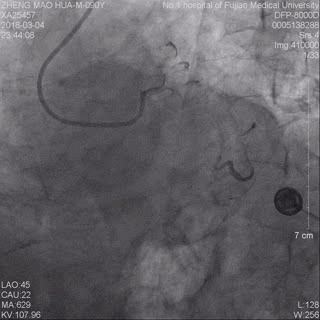

术前冠脉造影提示前降支近端急性闭塞 术后冠脉造影提示前降支血流通畅